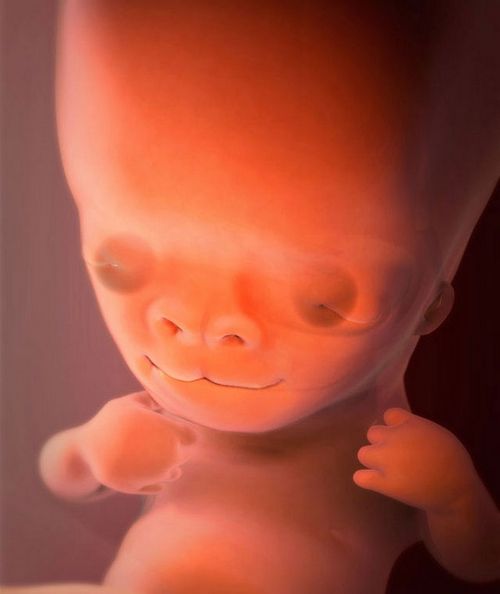

9 Тиждень вагітності вік плоду 7 тижнів

На 9-ій акушерської тижні вагітності майбутній малюк, незважаючи на свої невеликі розміри, все більше схожий на людину: у нього сформовані всі частини тіла, закладені основні органи, які протягом наступних місяців вагітності будуть ускладнюватися і рости.

На цьому терміні головка малюка ще непропорційно велика і притиснута до грудей, а його тіло починає потихеньку випростатися. Очки малятка вже сформувалися, але поки залишаються щільно закритими. Добре визначаються вушні раковини з формувалися мочками. Малюк вже вміє відкривати і закривати свій рот, може морщити губки. В цей же час з'являються зачатки майбутніх зубів.

Значні зміни відбуваються і в головному мозку: формується мозочок - найважливіший орган рівноваги, а також розвивається гіпофіз. Одночасно відбувається закладка черепних і спинномозкових нервів. До речі, існує цікава гіпотеза, що незвичайні смакові пристрасті вагітних пов'язані саме з тим, що формується мозок малюка намагається подавати мамі сигнали про свої потреби.

На 9-му тижні хвостик перетворюється в куприк, продовжують збільшуватися вже сформовані раніше кінцівки, причому малюк вже може ними ворушити, а також стискати кисті в кулак і розтискати їх. Всі ці дивовижні зміни можна спостерігати на ультразвуковому дослідженні, але сама мама поки не може відчути руху малюка.

Печінка маляти виконує найважливішу кровотворну функцію і починає продукувати лімфоцити - основні клітини імунної системи. Починають свої роботу нирки і щитовидна залоза, в якій вже продукуються гормони, практично сформовані зовнішні статеві органи.

У четирьохкамерному серце плоду відбувається формування клапанів його отворів. Биття маленького сердечка можна зафіксувати за допомогою апарату УЗД - на цьому терміні воно скорочується з частотою 150 - 170 уд / хв.

Фото плода на 9 тижні вагітності (вік плоду 7 тижнів)

На 9-му тижні плід розміром вже з виноградинку - його куприка-тім'яної розмір (КТР) становить від 2,2 до 3 см, розмір досягає 5,5 см. З Вага малюка коливається в межах 4 - 6 грам.